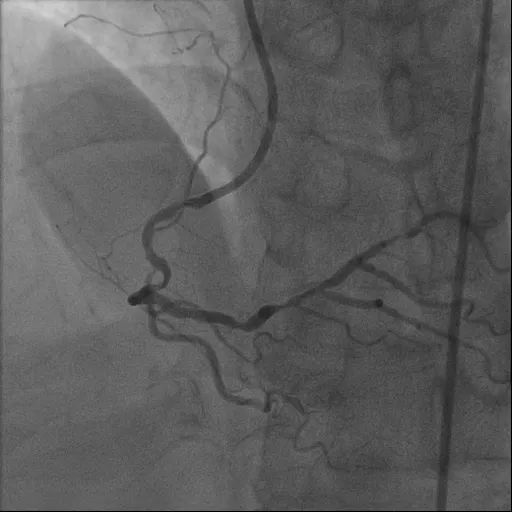

造影检查显示:冠状动脉三支病变。其中,右冠状动脉近中段狭窄钙化最重处约 90%,伴重度弯曲;左冠状动脉前降支近中段狭窄钙化最重处约 85%;左冠状动脉回旋支近段狭窄约 85%。

造影可见血管狭窄明显缓解,管腔面积得到有效恢复,血流通畅。